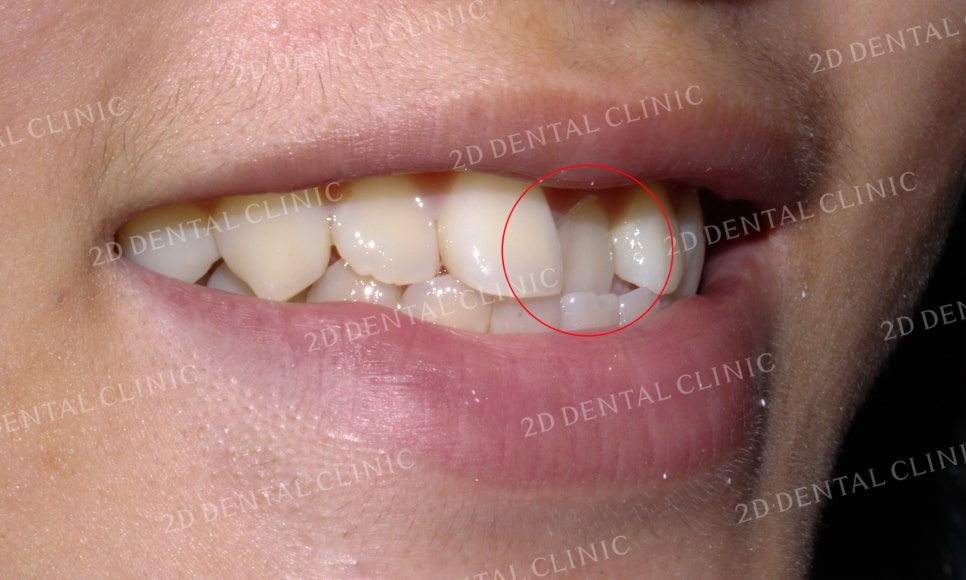

측면의 미소 시 모습입니다.

중절치가 완전히 안쪽으로

물리는 모습이 확인됩니다.